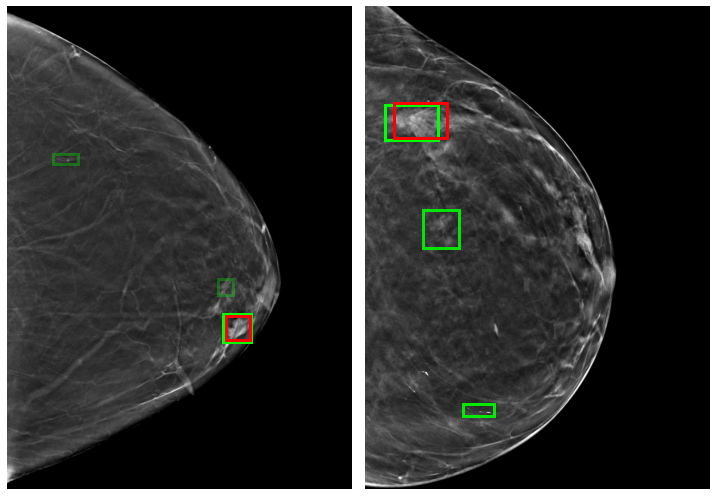

We discuss how we trained AI models on 3D mammograms and room for improvement.